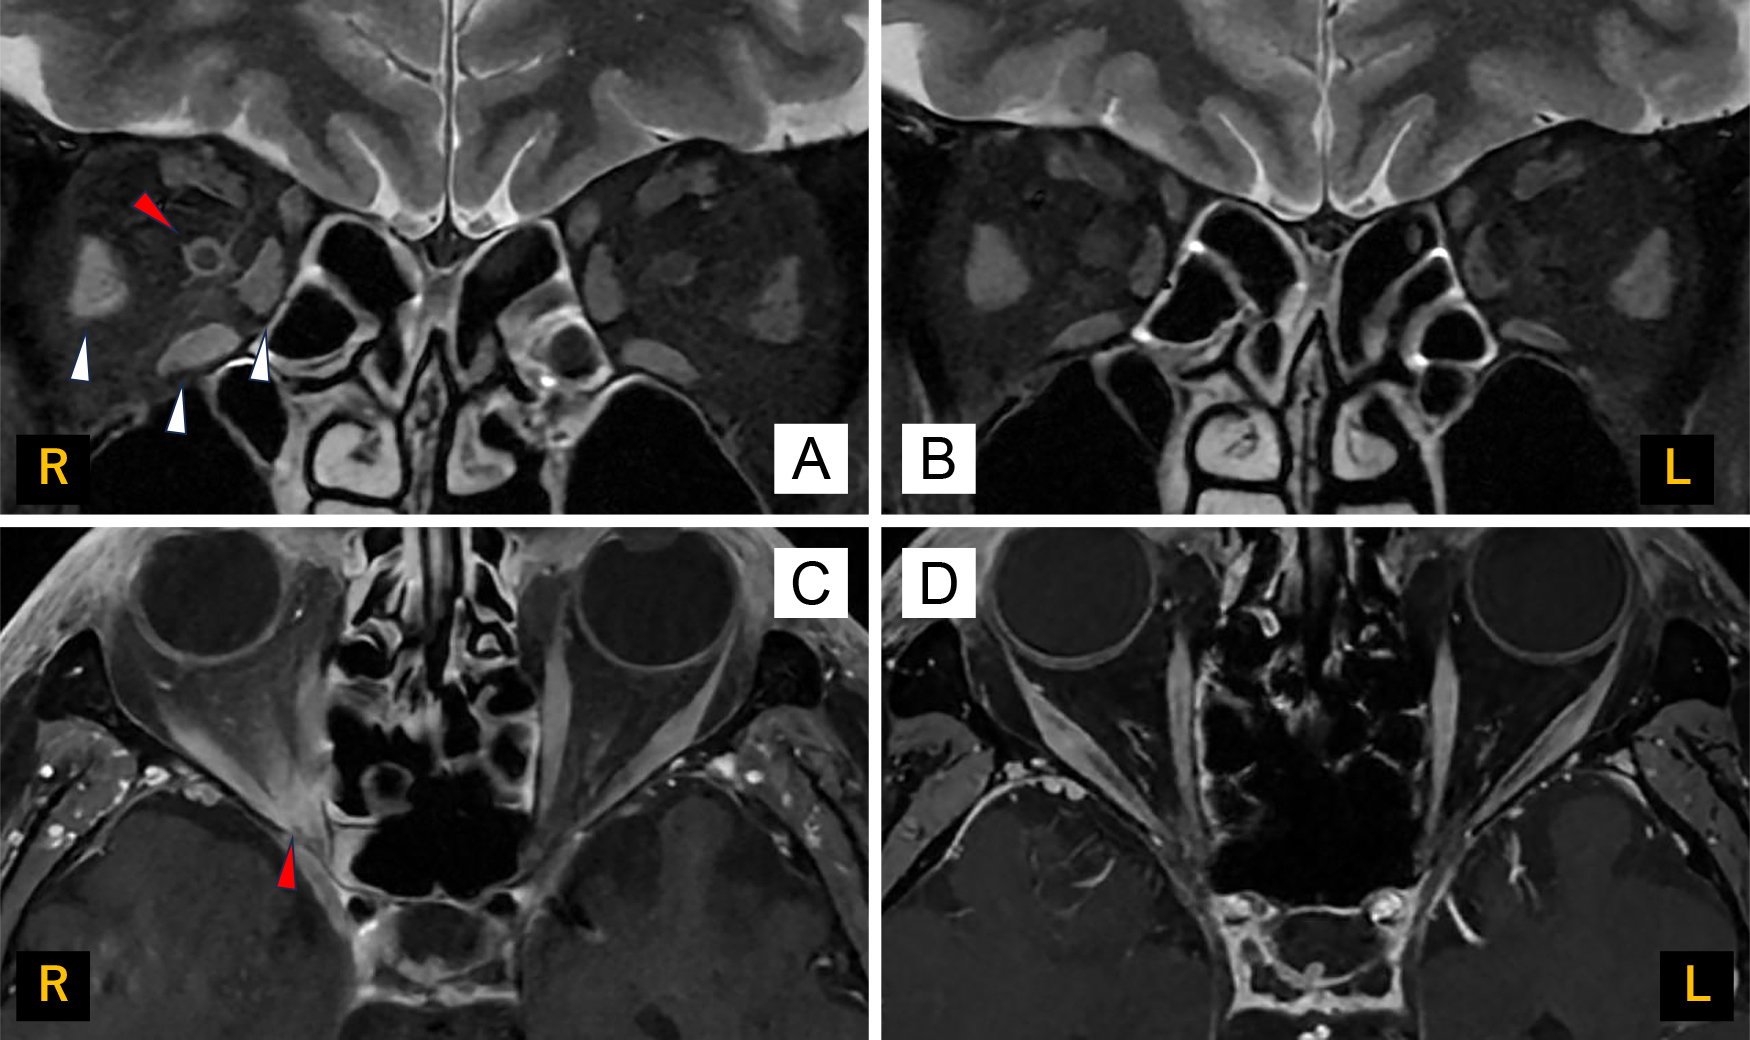

脊髄MRIや髄液検査で異常を認めなかった抗myelin-oligodendrocyte glycoprotein(MOG)抗体関連疾患の1例

A case of anti-myelin-oligodendrocyte glycoprotein (MOG) antibody-associated disease without abnormal findings on spinal MRI and cerebrospinal fluid examination

若月 里江, 武内 智康, 岡 耕太, 竹ノ内 晃之, 渡邊 一樹, 中村 友彦

Rie Wakatsuki, Tomoyasu Bunai, Kouta Oka, Akiyuki Takenouchi, Kazuki Watanabe, Tomohiko Nakamura

2026/03/11